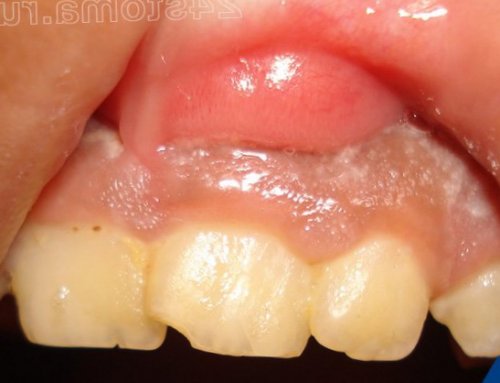

• ранее в проекции этого зуба на десне мог появляться свищ (рис.4),

• появлялась припухлость десны в проекции больного зуба (рис.5-6),